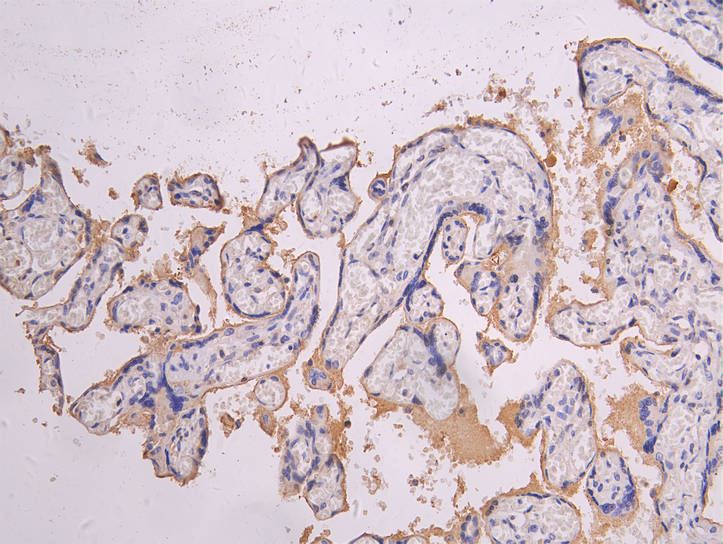

IHC image of CSB-RA835695MA1HU diluted at 1:200 and staining in paraffin-embedded human placenta tissue performed on a Leica BondTM system. After dewaxing and hydration, antigen retrieval was mediated by high pressure in a citrate buffer (pH 6.0). Section was blocked with 10% normal goat serum 30min at RT. Then primary antibody (1% BSA) was incubated at 4°C overnight. The primary is detected by a Goat anti-human polymer IgG labeled by HRP and visualized using 0.05% DAB.